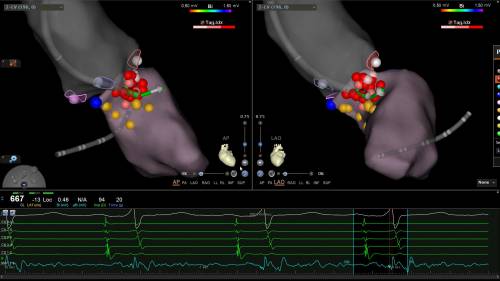

77岁的曹女士因反复晕厥、活动耐量下降曾就诊于湖南多家知名医院,多次就医均未找到解决办法。后在中南大学湘雅三医院心律失常心衰专科诊断为“梗阻型肥厚性心肌病并心房颤动”。张志辉教授带领的心律失常介入团队经充分讨论和研究,制定了“一站式”射频消融解决梗阻型肥厚性心肌病并心房颤动的治疗方案。随后,张志辉教授带领罗文治主治医师和邓煦主治医师为该患者实施了手术,患者上手术台即发作房颤,收缩压一度下降到60mmHg,手术在紧张的气氛中进行,面对手术的重重困难,凭借团队的丰富的临床经验及精湛的手术技巧,最终完成了房颤的环肺静脉隔离和左房基质改良术,并在左心室流出道梗阻部位也做了精准的射频消融,完美的避开了希氏束及左后分支,从而杜绝了严重房室传导阻滞的发生。术后在心内科13病区医疗和护理团队的悉心治疗下,患者身体状况恢复良好,术后2天的主动脉瓣压力阶差下降了26mmHg。曹女士生活质量得到明显改善,未来的生活重新迎来了灿烂的阳光。

据悉,肥厚型心肌病(HCM)是一种以心肌肥厚为特征的心肌疾病,主要表现为左心室壁增厚。临床可表现为心悸、胸痛、心力衰竭(心衰)及各种心律失常,伴有左室流出道梗阻(LVOTO)的患者在起立或运动时可出现眩晕、晕厥,甚至猝死。尤其HCM并发心房颤动时更加导致猝死和卒中发生率明显增加。对于存在LVOTO、有症状的HCM患者,外科手术曾被认为是非药物治疗的“金标准”,但创伤较大,导致三度房室传导阻滞等并发症风险较大。近年来,国内外尝试将射频消融的方法引入肥厚梗阻性心肌病的治疗,应用导管射频能量破坏引起梗阻的室间隔心肌。但因手术的难度和风险,在全国开展较少,梗阻肥厚性合并阵发性房颤的射频消融更是罕见,临床处理也极为棘手。